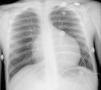

O eletrocardiograma (ECG) mostrou taquiarritmia de complexos estreitos, com frequência cardíaca entre 150‐180bpm, não revertida com adenosina, compatível com taquicardia ventricular. A telerradiografia torácica revelou cardiomegalia (índice cardiotorácico >0,6, Figura 1) e o estudo analítico, elevação das transaminases (TGO 94UI/L, TGP 72UI/L), do BNP (742pg/ml) e hiponatremia (133mEq/L). Os marcadores de necrose miocárdica foram negativos. O ecocardiograma transtorácico (Figura 2 A e B) mostrou dilatação e disfunção sistólica grave do VE (diâmetro telediastólico do VE de 65mm: z‐score+7,8; diâmetro telessistólico do VE de 60mm: z‐score+12,3, fração de ejeção do VE de 20% e fração de encurtamento do VE de 12%). Visualizou‐se trabeculação exuberante e recessos intertrabeculares profundos preenchidos por sangue das paredes lateral e região apical do VE, e a relação entre a espessura da camada não compactada e a espessura da camada compactada foi superior a 2, medido em incidência paraesternal eixo curto, em telessístole (segundo critérios de Jenni et al.).